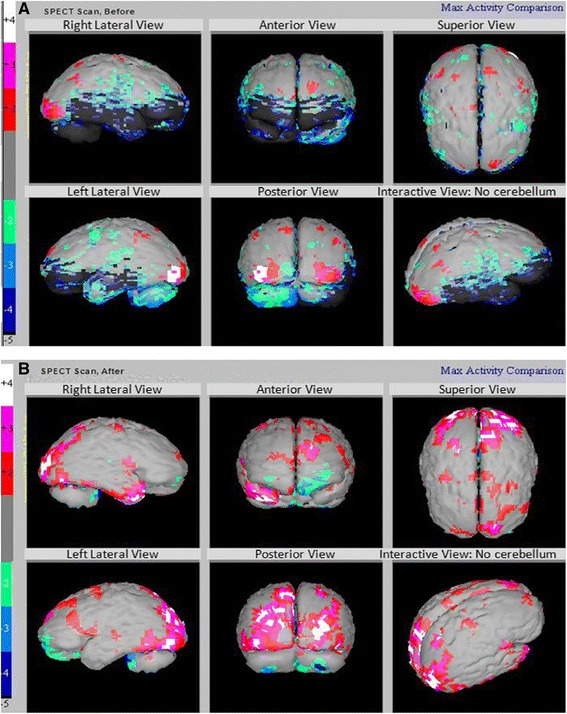

我們能夠在治療前后對所有患者進(jìn)行SPECT掃描?;颊叩腟PECT掃描顯示在接受hESC治療后灌注得到改善。我們一位患者的SPECT掃描報告如圖3A和B。

圖3:腦癱患者的 SPECT 掃描

圖3:腦癱患者的 SPECT 掃描(灰色 – 正常;紅色、粉紅色和白色 – 高于正常水平;綠色、淺/深藍色、黑色 – 低灌注)。

A)

在接受hESC治療之前顯示灌注不足的區域。

B)接受hESC治療后灌注改善(黑色區域減少)。